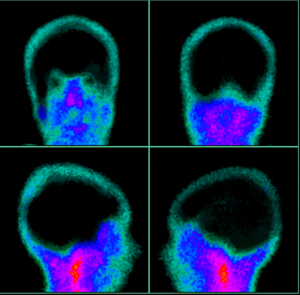

Medical-Surgical Nursing

Cheatsheets

226

Mnemonics

84

Images

318

Picmonic

0